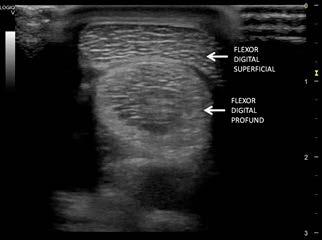

MINERALIZAREA TENDONULUI MUȘCHIULUI SUPRASPINOS LA CÂINEASPECTE ECOGRAFICE ȘI RADIOLOGICE: PREZENTARE DE CAZ

MINERALIZED SUPRASPINATUS TENDON IN DOGS - ULTRASOUND AND RADIOLOGICAL ASPECTS: CASE REPORT Andreea Istrate, R. Constantinescu, Alexandra Peteoacă, A. Tănase